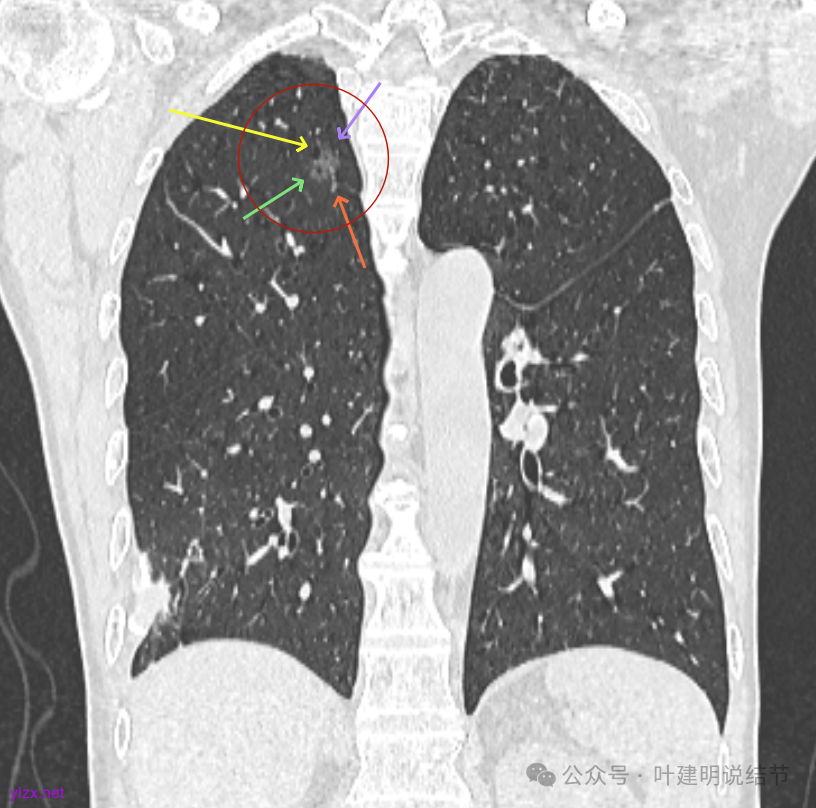

最后看2025年3月的连续层面的影像细节:

右上病灶淡磨密度,有空泡征,整体轮廓较清。

瘤肺边界清楚,空泡征明显。

表面不平,没有实性成分。灶内空泡有些像蜂窝状。

病灶边上有小血管走行,整体轮廓清,没有明显实性成分。

右上病灶淡而纯主要原因,空泡征明显。

右上冠状位显示病灶纯磨,血管进入穿行,灶内空泡征,表面毛刺征,没有明显实性成分。

左上病灶冠状位显示纯磨,部分连续细毛刺,灶内有扩张的细支气管似的,整体轮廓清。